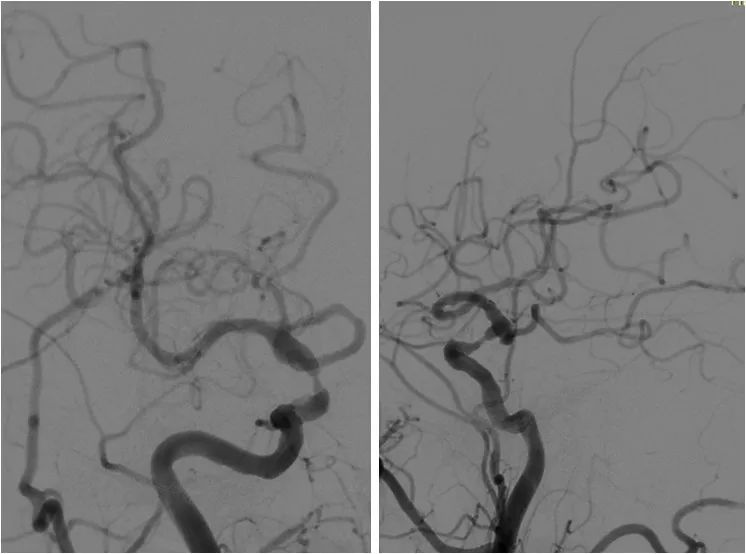

DSA:右颈内动脉C6段重度狭窄;双侧胚胎型大脑后动脉;左椎动脉V1段迂曲,V4段重度狭窄;右椎动脉纤细,V4段以远显影欠佳(图3-6)。

图3

图4